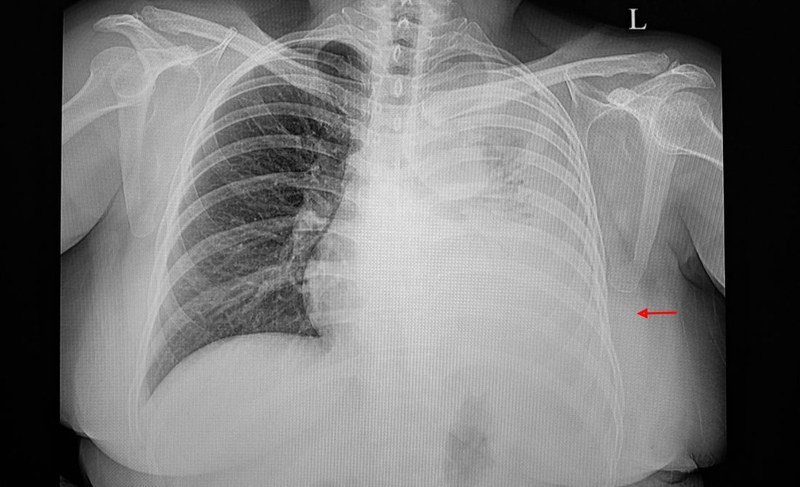

Vị trí đặt ống dẫn lưu sẽ được bác sĩ xác định dựa trên nguyên nhân gây tràn khí, tràn dịch và kết quả hình ảnh (chụp X-quang, siêu âm). Vị trí đặt ống dẫn lưu được xác định dựa trên nguyên nhân bệnh lý. Trong tràn khí màng phổi, ống thường đặt ở khoang liên sườn 2 - 4 đường trung đòn, còn trong tràn dịch hoặc tràn mủ, ống thường đặt ở khoang liên sườn 5 - 7 đường nách giữa hoặc sau. Quy trình kỹ thuật dẫn lưu màng phổi thường được thực hiện dưới hướng dẫn của siêu âm hoặc X-quang để đảm bảo chính xác. Các bước thực hiện chi tiết như sau: